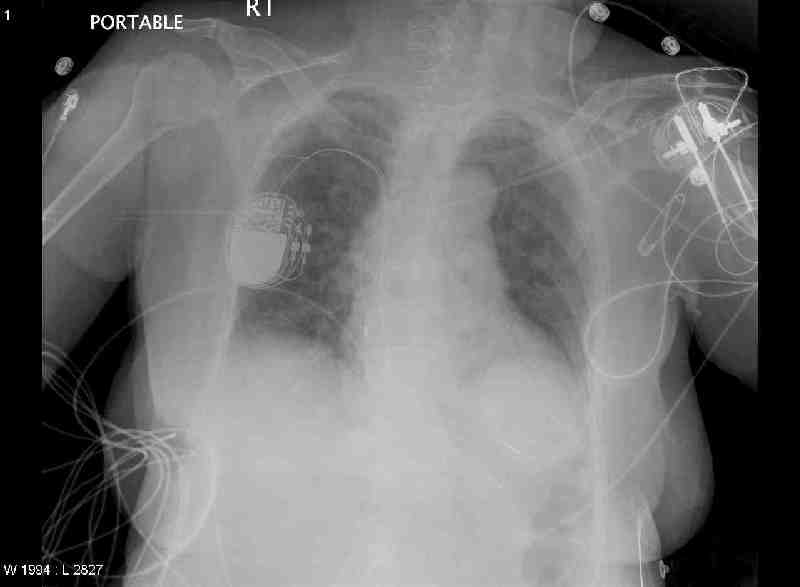

CXR Day 0 (admission day) 8:30pm

Study Description: CHPORT

Reason for Study: LINE REPLACEMENT

Body

The chest is overall improved since the previous study with a

new left subclavian line in place. No evidence for pneumothorax is present.

Pacemakers in place.

Impression: good position of the central line.